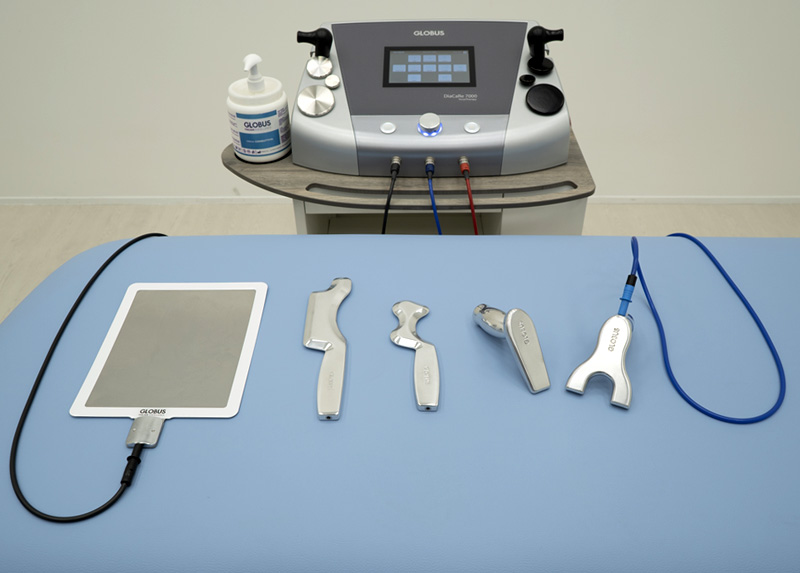

רדיו-פרקונסיה (Tecar)

עובד על עומק הרקמות, משחרר נוקשות ומסייע בשיקום מהיר יותר

עובדים עם המכשור המתקדם בעולם

טכנולוגיה מהתקדמות בעולם

הקליניקה מצוידת במכשור חדשני כמו TECAR, לייזר רפואי, מציאות מדומה ועוד, כלים שלא תמצאו במרפאות ציבוריות